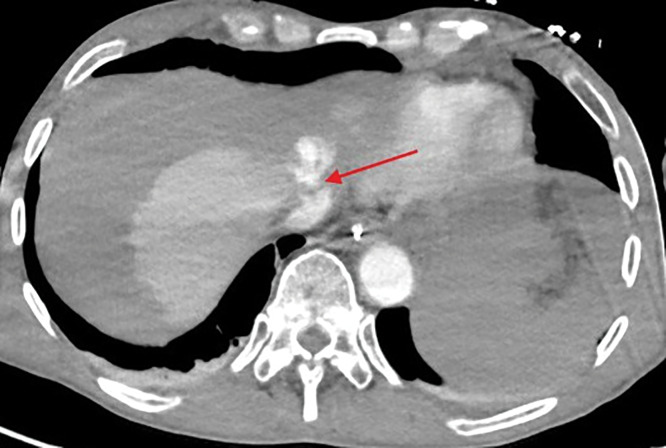

Teaching point: Laceration of the left hepatic vein is a rare but potentially fatal complication of cardiopulmonary resuscitation (CPR) and should be considered in patients with unexplained hemodynamic instability following resuscitation.

Abstract Image